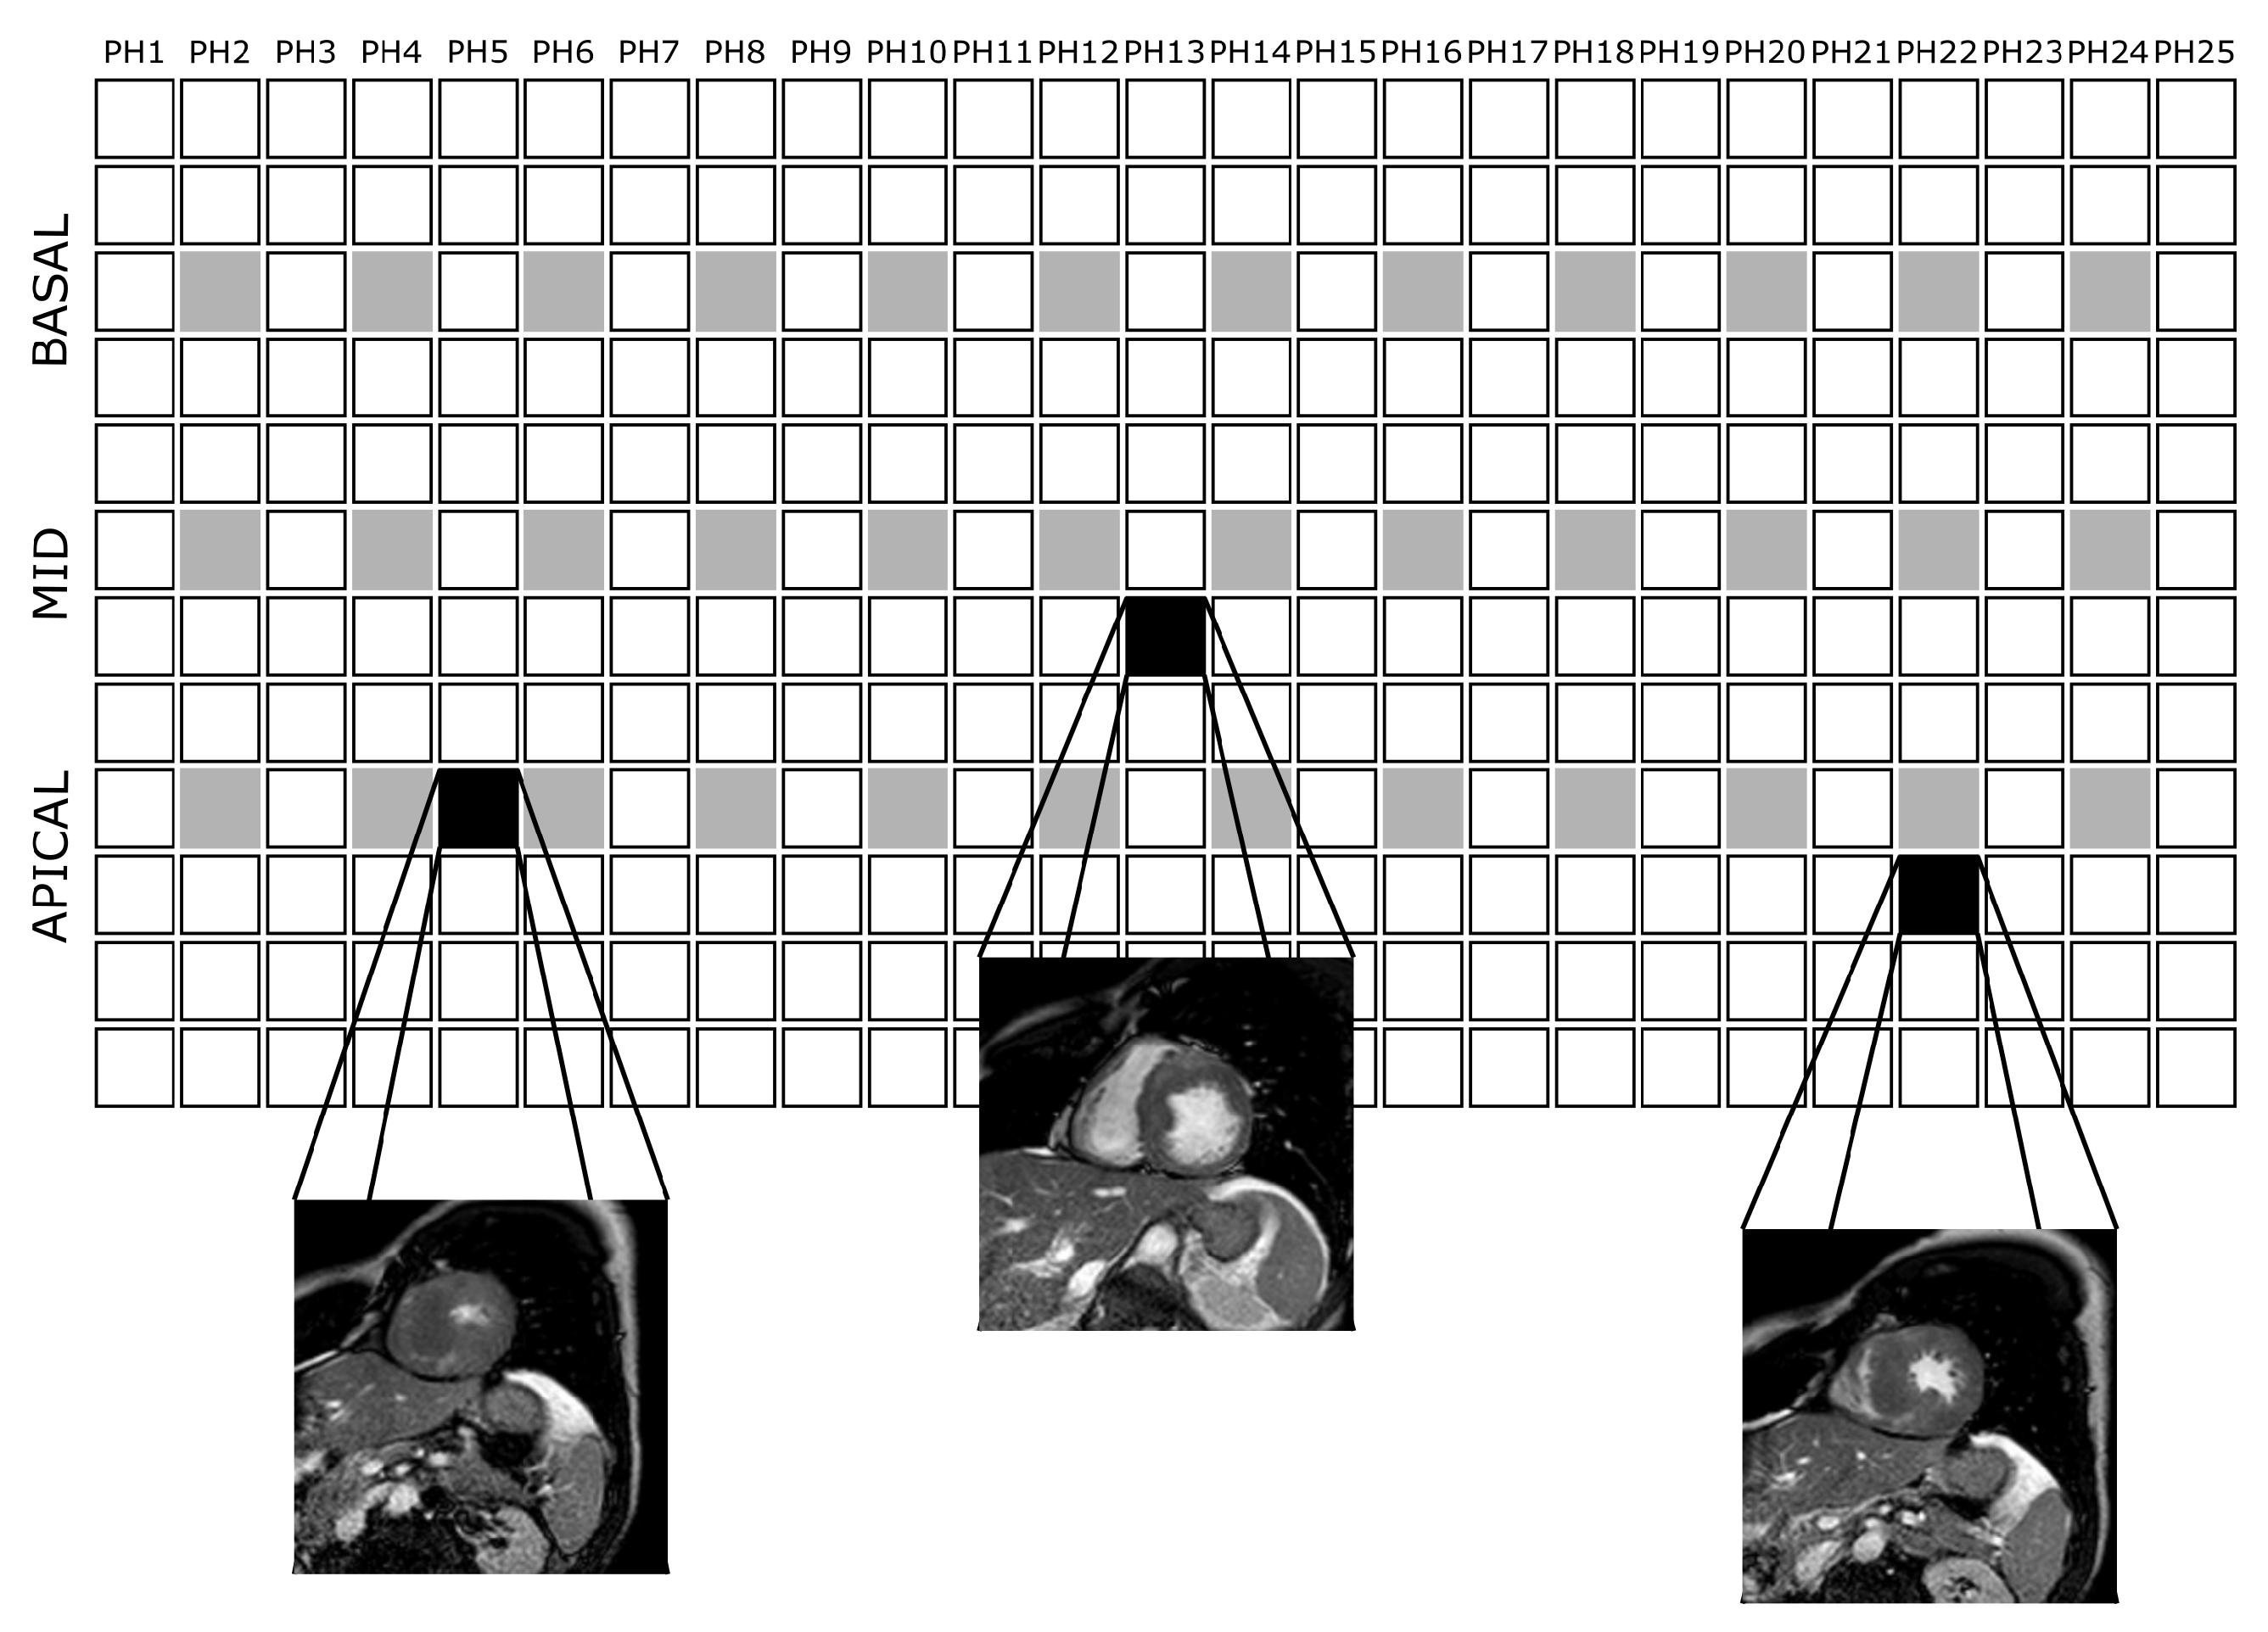

Appendix C. Example Images